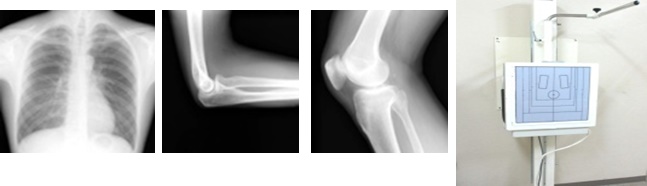

X線単純撮影検査

X線単純撮影は症状に応じて第一に行われる検査です。X線を使用して胸部・腹部・骨などの撮影を行い、CR(デジタルX線画像診断)システムを用いて撮影データをコンピュータ処理することにより高画質の画像を提供します。